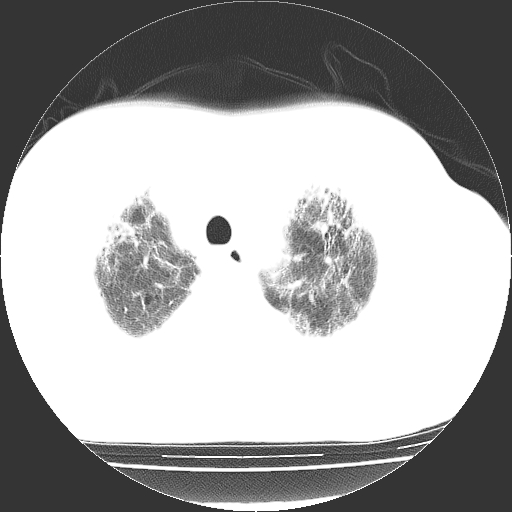

男,68岁,咳嗽、胸闷、发烧三天,查体:双肺散在湿罗音。

首先考虑特发型肺间质纤维化;两侧少量胸腔积液。

依据:1、两肺广泛条索状、网格状、蜂窝状改变。

双肺多发条索状、网格状及小灶状密度增高影。考虑慢支合并感染.间质纤维化,双侧少量胸腔积液

两肺广泛条索状、网格状、蜂窝状改变。肺间质纤维化,肺心病,双侧胸腔积液